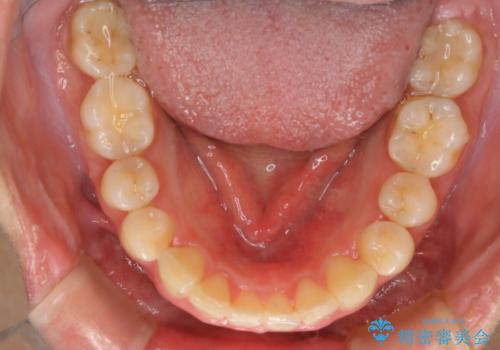

顔貌写真でも明らかに口の閉じやすさやEラインが改善している様子が分かります。

インビザラインで口元の変化

インビザラインの登場により抜歯以外の3種類の方法を効率よく活用することができるようになりました。

そのため、非抜歯でも口元の環境が改善するケースがあります。